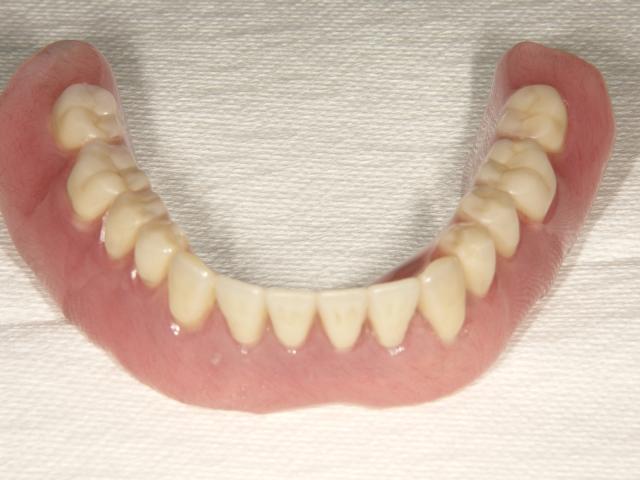

術後

ノンクラスプデンチャー ノンクラスプデンチャー ノンクラスプデンチャー

以前は金属のクラスプを使用した義歯使用していたが、今回ノンクラスプデンチャーに変更。

ややきつい感じがするが非常に軽くしっくりしているとの事!

五十嵐先生良かったね!!